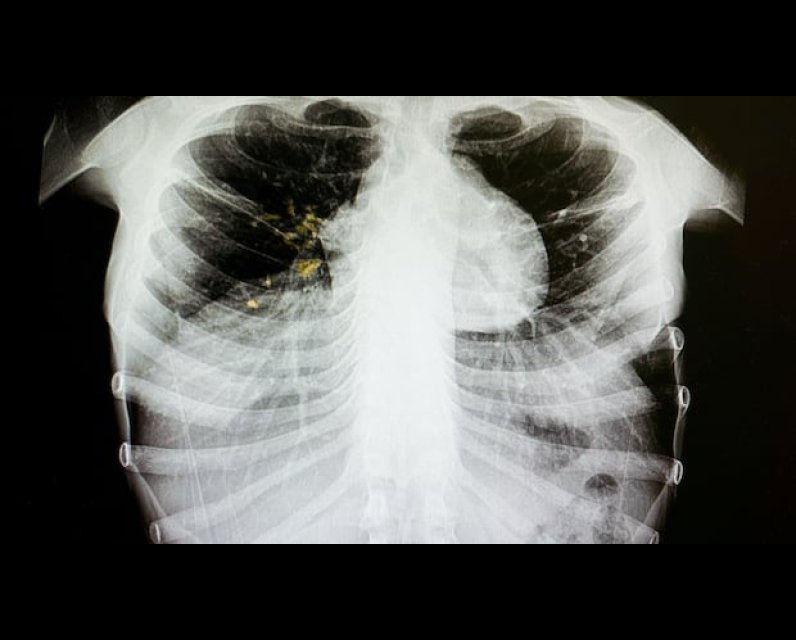

Edmonton doctor says inner-city TB outbreak low risk to general public

The head of Alberta's tuberculosis clinic says an outbreak in Edmonton's inner-city is is of little risk to Edmontonians at large.